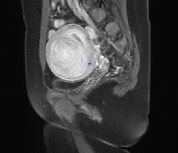

Imaging Outcomes

Figure 4. (A-D). Contrast-enhanced MRI obtained from a 35-year old patient with uterine fibroid. (A). Pre-HIFU MRI showed a significant enhancement of a uterine fibroid located at the anterior wall of the uterus, and the size of the fibroid was 5.6 cm x 4.6 cm x 4.9 cm; (B).1-day post-HIFU MRI showed no enhancement of the treated fibroid, the uterine fibroid was completely ablated; (C). 4-month post HIFU MRI showed the size of the treated fibroid reduced to 5.0 cm x 4.3 cm x 4.2cm, the shrinkage was 28.5%; (D). 10-month post-HIFU MRI showed the size of the treated fibroid reduced to 3.5 cm x 3.0 cm x 3.2cm, and the shrinkage was 73.4% compared to baseline. Images courtesy Prof. Zhang Lien.